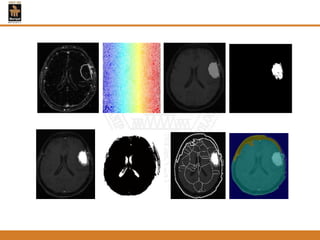

Figure1: Fuzzy C-means clustering (FCM) applied to the MRI

Figure 2: A level set segmentation

Figure 3:The final result